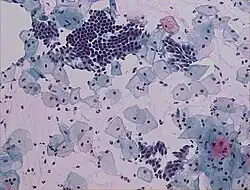

O teste de Papanicolau ou citologia cervical,[1] é um exame ginecológico de citologia cervical realizado como prevenção ao câncer do colo do útero.[2][3]

Consiste basicamente na coleta de células do colo uterino com uma espátula especial e o material é colocado em uma lâmina e analisado inicialmente ao microscópio por um citotécnico, sendo o resultado necessariamente liberado por um médico citopatologista, haja ou não alguma alteração no exame inicial ao microscópio, ou então diretamente por um citotecnologista (biólogo, biomédico ou farmacêutico) e posteriormente revisto por um médico citopatologista para emissão do diagnóstico, apenas nos casos positivos. É um exame citológico, examina a morfologia das células da mucosa do colo do útero, analisa alterações nas células cervicais, chamadas de displasia cervical. A displasia que se desenvolve deve-se a uma infecção causada pelo vírus que se designa papiloma vírus humano (HPV). Este vírus altera de tal forma as células que se podem formar tumores benignos ou mesmo malignos. Duas vacinas já são oferecidas, em clínicas particulares, na maior parte da América Latina, EUA e Europa. No Brasil, desde 2014, a vacina tetravalente (contra quatro tipos de vírus) é oferecida na rede pública para meninas entre 9 e 14 anos e, desde 2017, para meninos de 12 a 13 anos.[5]

O teste na maioria das vezes é um exame de triagem. Desta maneira nem sempre define diagnósticos definitivos, mas levanta suspeitas. Nestes casos, é necessária a confirmação por outros métodos.